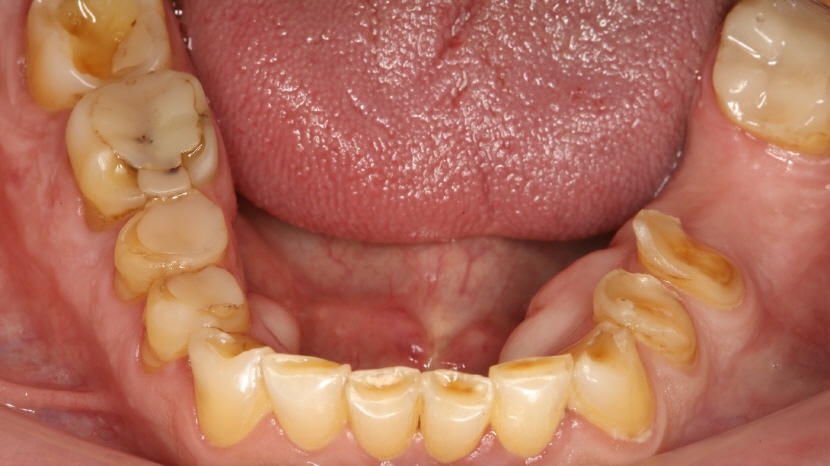

• Aufbissansicht Unterkiefer

Auch im Unterkiefer ist der Substanzverlust deutlich sichtbar. Ebenfalls sind die insuffizienten Füllungen gut sichtbar